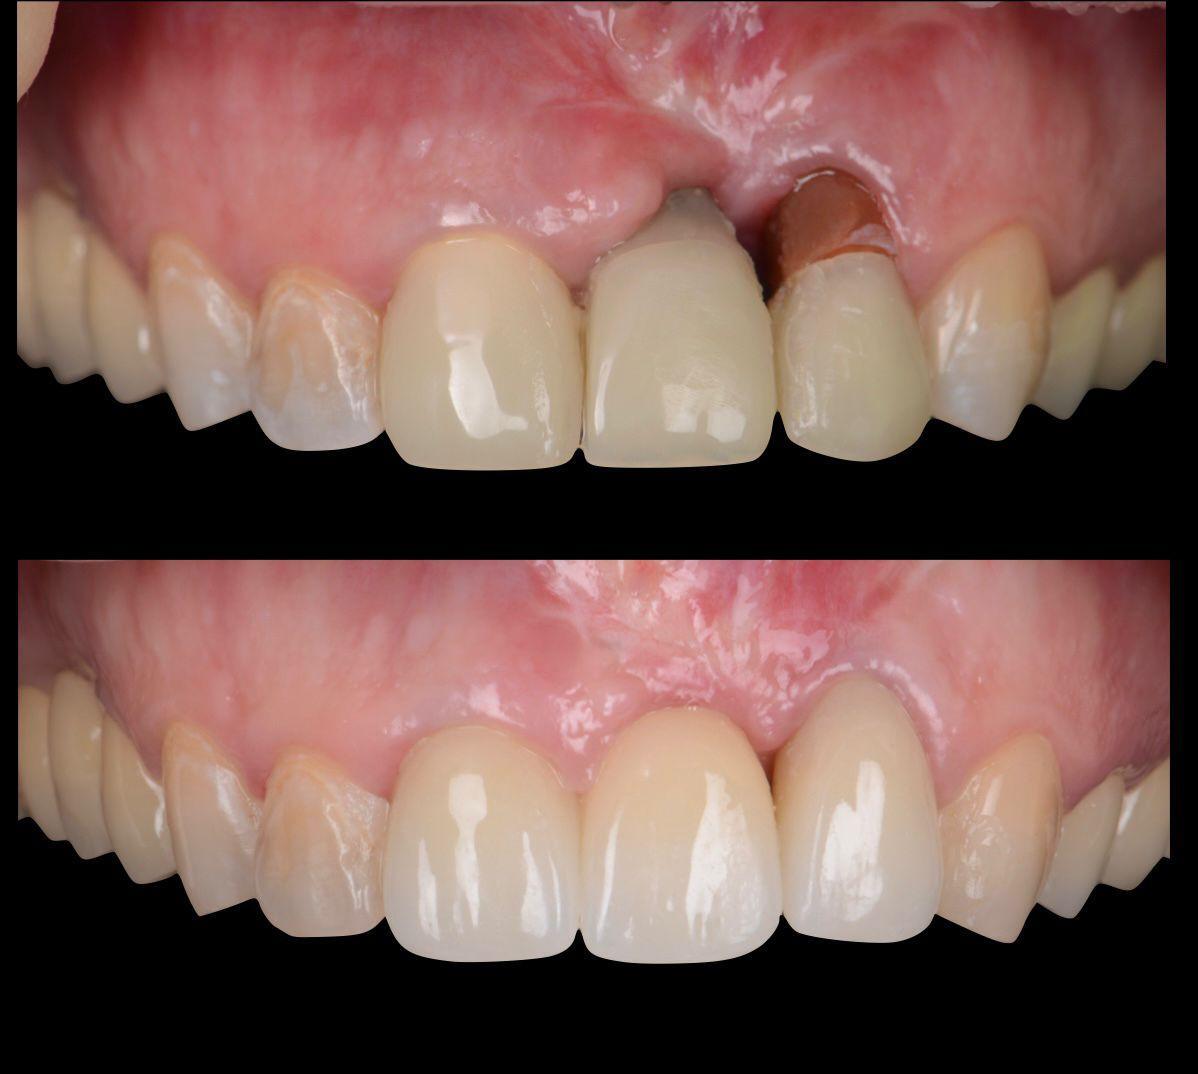

Устранение эстетических осложнений в области имплантатов. Преимущества методики VISTA

Лекция посвящена современным подходам к коррекции эстетических недостатков в области мягких тканей вокруг зубных имплантатов. Будет рассмотрена методика VISTA (Vertical Incision Subperiosteal Tunnel Access), как минимально инвазивный способ работы с мягкими тканями. Обсудим ключевые преимущества: снижение травматичности, высокую предсказуемость результатов и улучшение эстетики в зонах улыбки. Особое внимание уделим выбору донорских материалов, работе с сосудистой сетью и нюансам заживления. Лекция будет сопровождаться клиническими примерами и практическими рекомендациями для применения метода в повседневной практике.

До

После